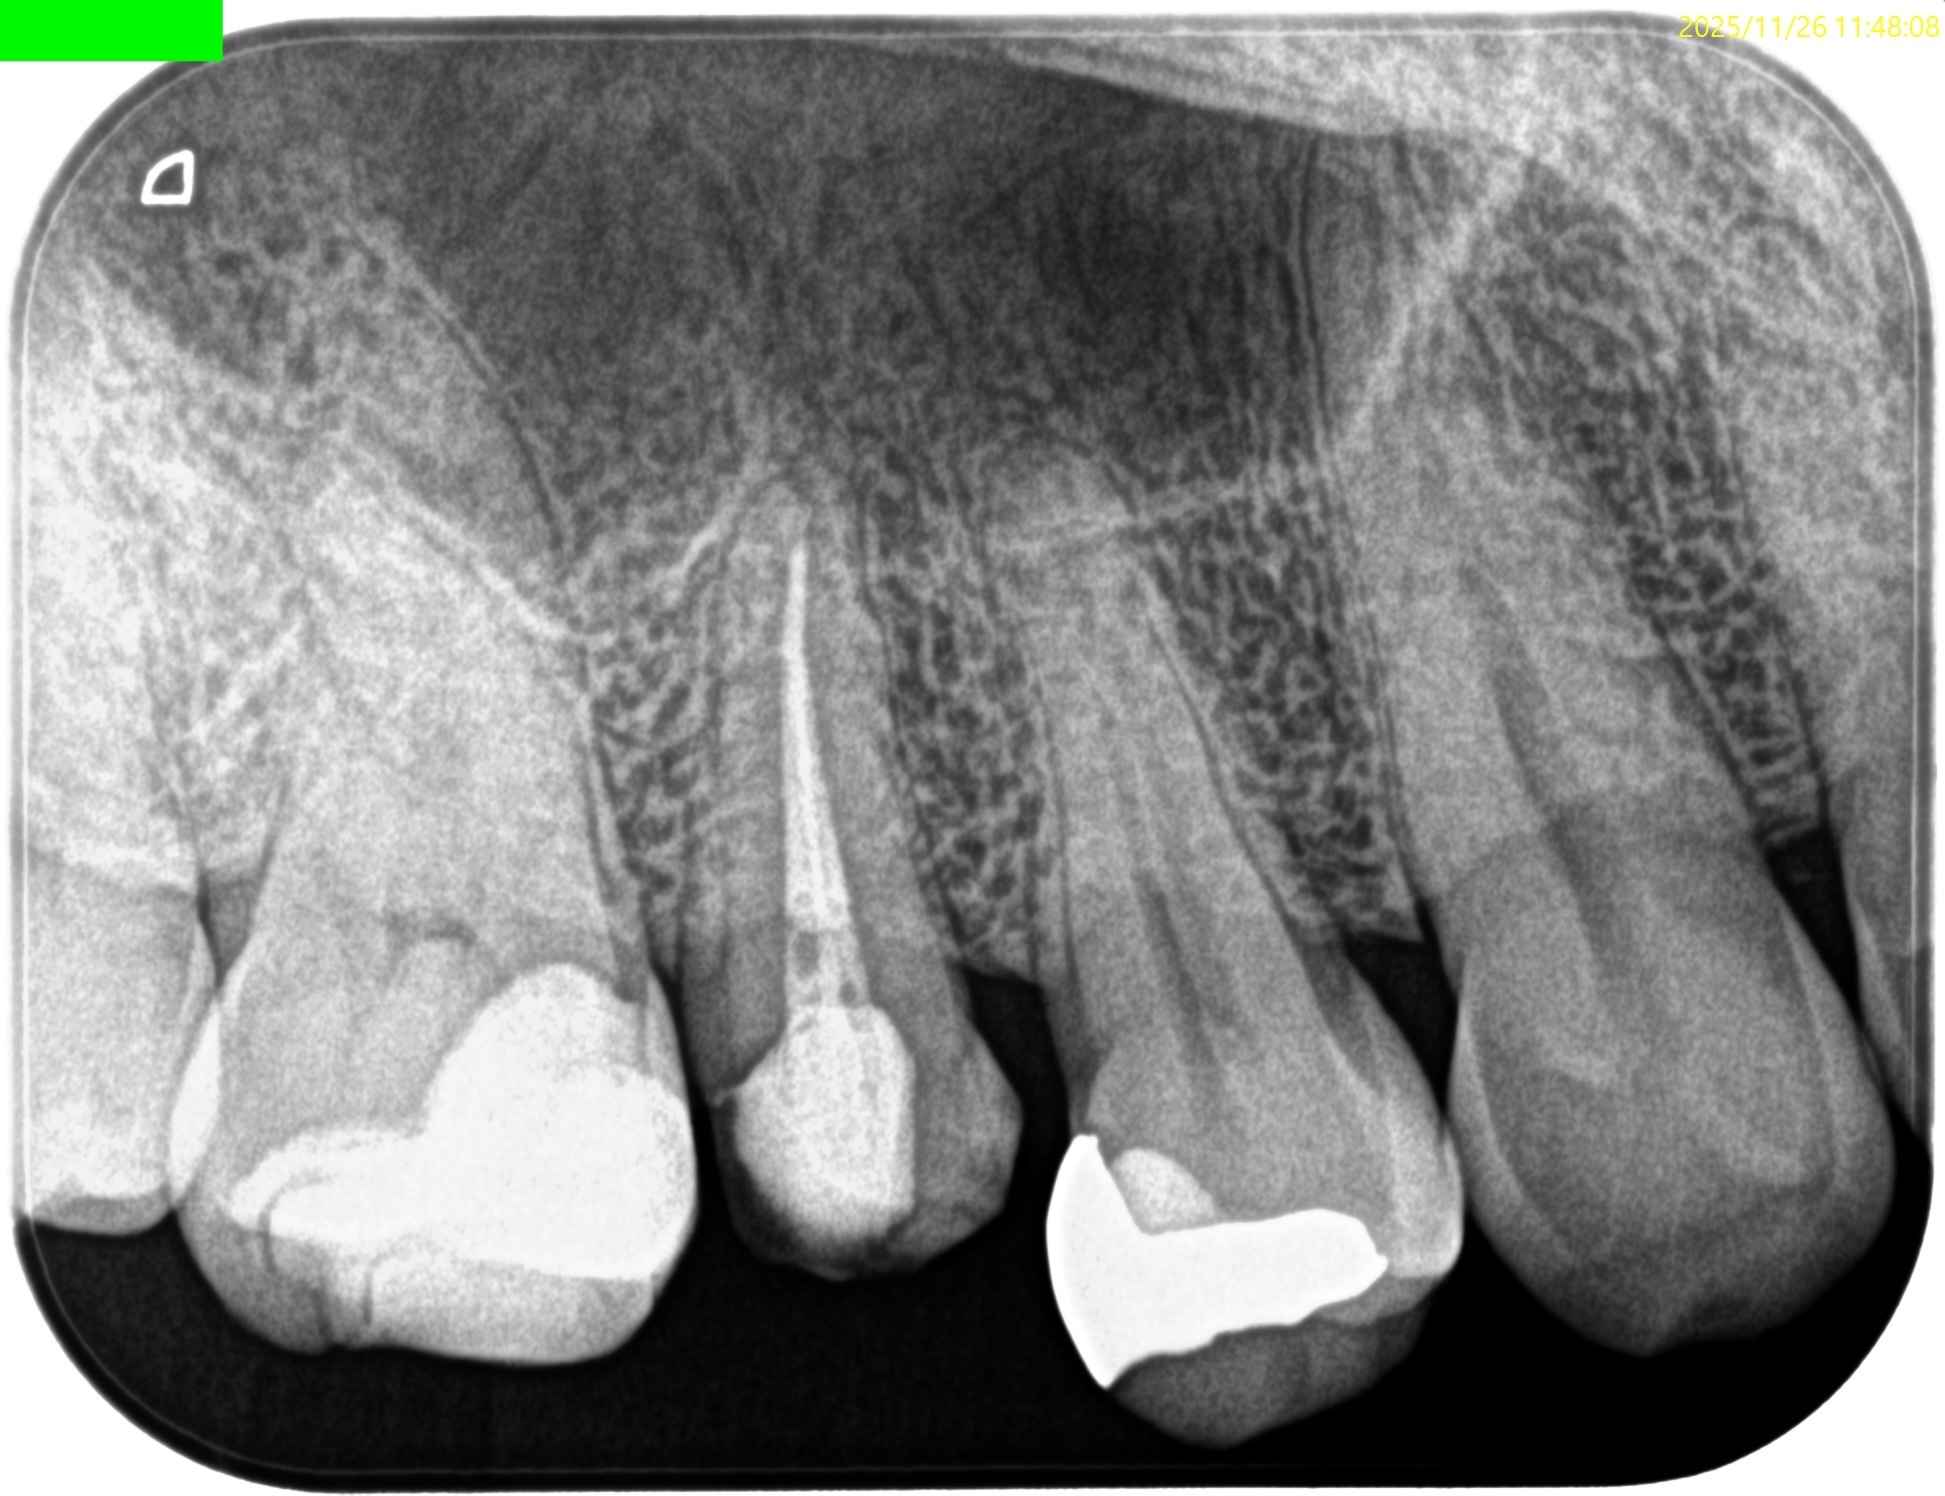

Pre-op Endo test(2025.11.26)

#4に咬合痛があるような…ないようなという感じであった。

病変のない、Initial RCTだ。

Pulp Dx: Asymptomatic irreversible pulpitis

Periapical Dx: Symptomatic apical periodontitis

Recommended Tx: RCT

#4 RCT(2025.11.26)

術後にPA, CBCTを撮影した。